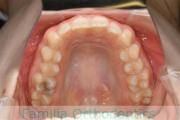

- ≫治療前

上顎

下顎

前歯の関係など

- ≫治療中 ステップ1

- ≫治療後